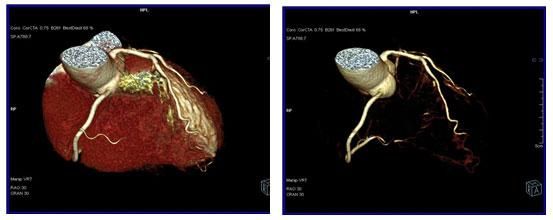

64排螺旋CT冠狀動脈血管成像:

1、簡單:無需經動脈插管,隻需象平時靜脈輸液一樣在肘靜脈内推注相對适量對比劑,然後行快速掃描即可完成整個檢查。

2、安全:64排螺旋CT冠狀動脈造影,對比劑用量較少,無需動脈插入導管,患者無需承擔麻醉及動脈插管等帶來并發症的危險。在冠狀動脈血管疾病的篩查、早期診斷、冠狀動脈成形術和搭橋術前、術後血管評價,冠狀動脈起源異常及心肌橋等方面極具優勢。

3、後處理功能豐富:西門子公司爲SOMATOM Definition AS+ 128層4D螺旋CT配備了功能強大的後處理工作站:MMWP(多産品工作站)和最新型的醫學影像IT工作平台,Syngo.via,智能,便捷。